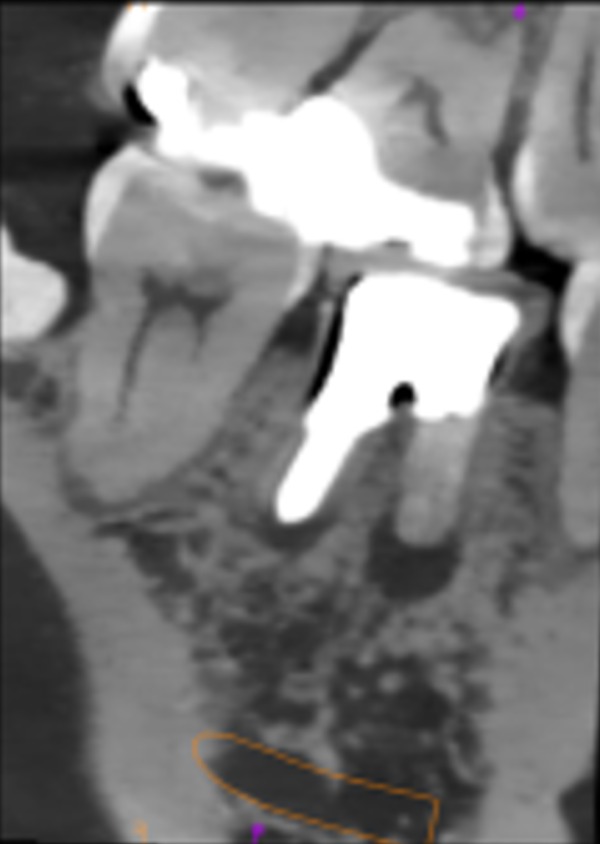

治療前のレントゲン写真は、こちらです。

まず抜歯を行い、その後に不良肉芽というものを新鮮な骨が見えるまで徹底的に掻き出します。その後、骨をドリルで掘っていき、必要な穴の径になったらインプラントを埋入していきます。インプラントが既定のトルクを獲得できた後、余ったスペースに人工骨を入れていきます。その後、人工骨がこぼれないようにメンブレンと呼ばれる膜を張り、歯肉を縫合します。術後1週間で糸を取り、術後3~4週間したらメンブレンを取ります。その後はクリーニングと確認を月に1回行い、術後3ヶ月後には型取りを行い、歯を装着していきます。